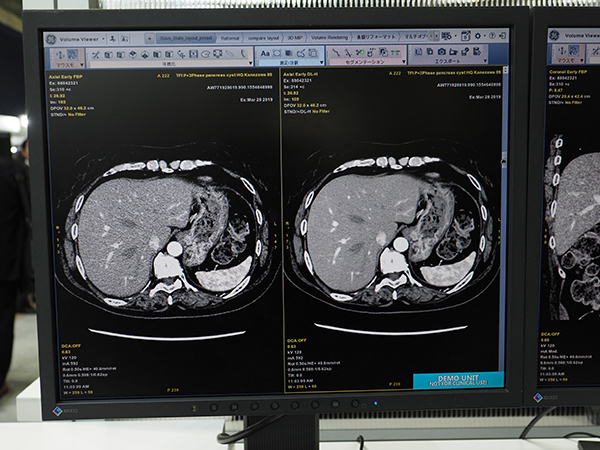

CTの展示エリアで最も注目を浴びていたのが,Edison Platformで開発されたCT画像再構成技アルゴリズム“TrueFidelity”である。今回のITEMに合わせて発表した,GEヘルスケア・ジャパンが最も力を入れてPRした展示の一つだ。

TrueFidelityは,ディープラーニングを用いて開発されており,従来の画像再構成技術とは一線を画している。CTの画像再構成技術は,近年医療被ばくへの社会的な関心が高まる中,低線量でも高画質を得るために,各社が力を入れて開発を進めてきた。GEでは,画像再構成技術として“ASiR”や“Veo”,両者を組み合わせた“ASiR-V”をCTに搭載し,医療被ばくの低減の貢献してきた。しかしながら,従来の画像再構成技術を用いたCT画像は,画質が読影する医師にとって違和感のあるテクスチャとなってしまい,特にノイズを低減すればするほど,その傾向が強くなってしまうという課題があった。

そこで,TrueFidelityでは,1970年代からCTを市場に送り出してきたGEがこれまで培ってきた画像再構成技術と,蓄積してきた画像データが生かされている。日本のエンジニアも参加しており,日本をはじめ,世界中の医師からのフィードバックを基に,FBP法で高線量で撮影した診断に適した画像を教師画像としてディープラーニングを行った。これにより,大幅に線量を落としても,高線量で撮影を行ったような鮮明な画質を得ることができる。また,全身の撮影に適用できるのも,TrueFidelityの特長である。特に,高い密度分解能が要求される頭部や腹部領域の検査で,画質を維持しつつノイズを低減し,読影する医師の負担軽減や診断能の向上に寄与する。放射線被ばくの感受性が高い小児検査でも大幅な被ばく低減が可能となる。

TrueFidelityは,ハイエンド装置の「Revolution CT」に搭載可能である。オプションとして提供されるほか,すでにRevolution CTを導入している施設には,アップグレードで対応する。Revolution CTは,RSNA 2013で発表され,2014年のITEMでお披露目された。高画質,ワイドカバレッジ,ハイスピードをコンセプトに開発され,その後,dual energy CT技術“GSI Xtream”を搭載するなど,進化を続けている。今回のTrueFidelityへの対応も,Revolution CTの大きな進化と言えるだろう。

Edison Platformの“TrueFidelity”

“TrueFidelity”(右)は大幅にノイズ低減を実現